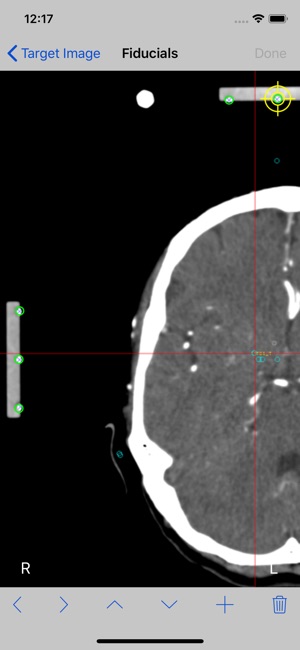

StereoCheckRM work with axial (transverse) slices only, there is no support for coronal or sagittal views.

The mathematical algorithm used by StereoCheckRM includes corrections for tilted images (rotation around X and/or Y axis) as long as nine fiducials are present in the image. There is correction for rotation around Z up to 5 degrees. Linear image distortions are also corrected.

6. Set the point-of-view of the image if necessary. Tap Done button.

7. Mark each fiducial on the image. StereoCheckRM use nine (9) fiducials. Tap the Done button.